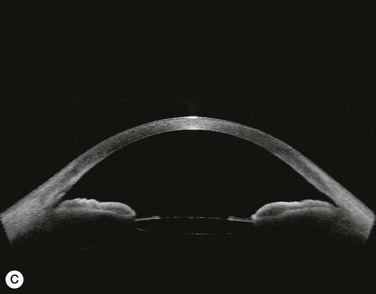

Several studies have shown that extracapsular cataract extraction (ECCE) with IOL implantation is effective in opening the angle and controlling IOP in refractory PAC.27–30 Currently, ECCE has been replaced by phacoemulsification which offers a higher surgical success rate, less postoperative inflammation and fewer complications. In addition, the clear corneal approach spares the superior conjunctiva for possible filtering surgery, if needed. Phacoemulsification and IOL implantation has been reported to be highly effective in patients with uncontrolled PAC.31,32 However, up to 32% of the patients still had persistent PAS and required long-term treatment with glaucoma medication following lens removal either by ECCE or phacoemulsification and IOL implantation alone (Fig. 108-2A).5,32 Goniosynechialysis is the next step to eliminate the remaining synechiae and control the IOP (Fig. 108-2C).

Goniosynechialysis becomes more effective when performed after lens removal. An increase in the anterior chamber space provides ample room to perform the procedure and reduces the chance of synechial reformation. Combined phacoemulsification and GSL (phaco-GSL) has been shown to be safe and highly effective in controlling IOP (<21 mmHg) and decreasing PAS in >90% of 52 eyes that developed acute PAC within 6 months and had persistent IOP elevation following laser treatment.26,33,34 Postoperative IOP was reduced to below mid-teens regardless of the preoperative IOP level. Recurrence of the PAS, although uncommon, might occur during the first three months. The success of phaco-GSL has been stable since the third postoperative month for up to 14 years, providing a long-lasting control or even a permanent cure.26 A recent multicenter study also demonstrates a success rate (< 21 mmHg) of 85.9% in 109 eyes with uncontrolled PAC/PACG at one and three years following phaco-GSL.35

Patients are treated with antiglaucoma medications and frequent topical steroids. When the inflammation subsides, the medications are then slowly tapered off within a month. Occasionally, a release of aqueous through the paracenteses at the slit lamp may be performed if a high IOP rise occurs. Gonioscopy typically reveals opening of the angle structures with irregular pigmentation on the newly exposed trabecular meshwork and the angle wall (Fig. 108-6). Angle recession or a cyclodialysis cleft are undesirable findings. If successful, anterior segment optical coherence tomography or ultrasound biomicroscopy should demonstrate separation of the PAS and reopening more than half of the entire angle (Figs 108-2, 108-7).